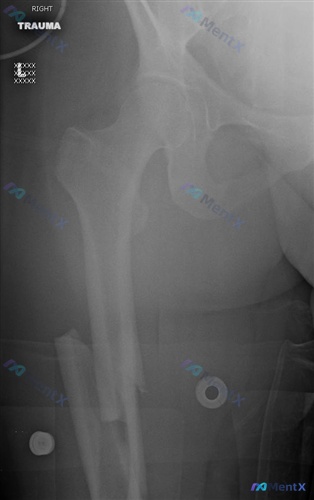

影像核心表现(右侧大腿正位X光)

- 骨折征象:右侧股骨干中下段可见明显骨皮质连续性中断,属于横断性骨折(伴有斜行成分);

- 断端情况:远折端相对于近折端向外侧及上方移位,骨折断端重叠;

- 排除情况:股骨近端(股骨头、颈、大小转子)形态正常,右侧髋关节对位良好,未见明显脱位;骨密度尚可,未见溶骨性/成骨性破坏病灶或典型骨膜反应;无明显病理性骨折提示。